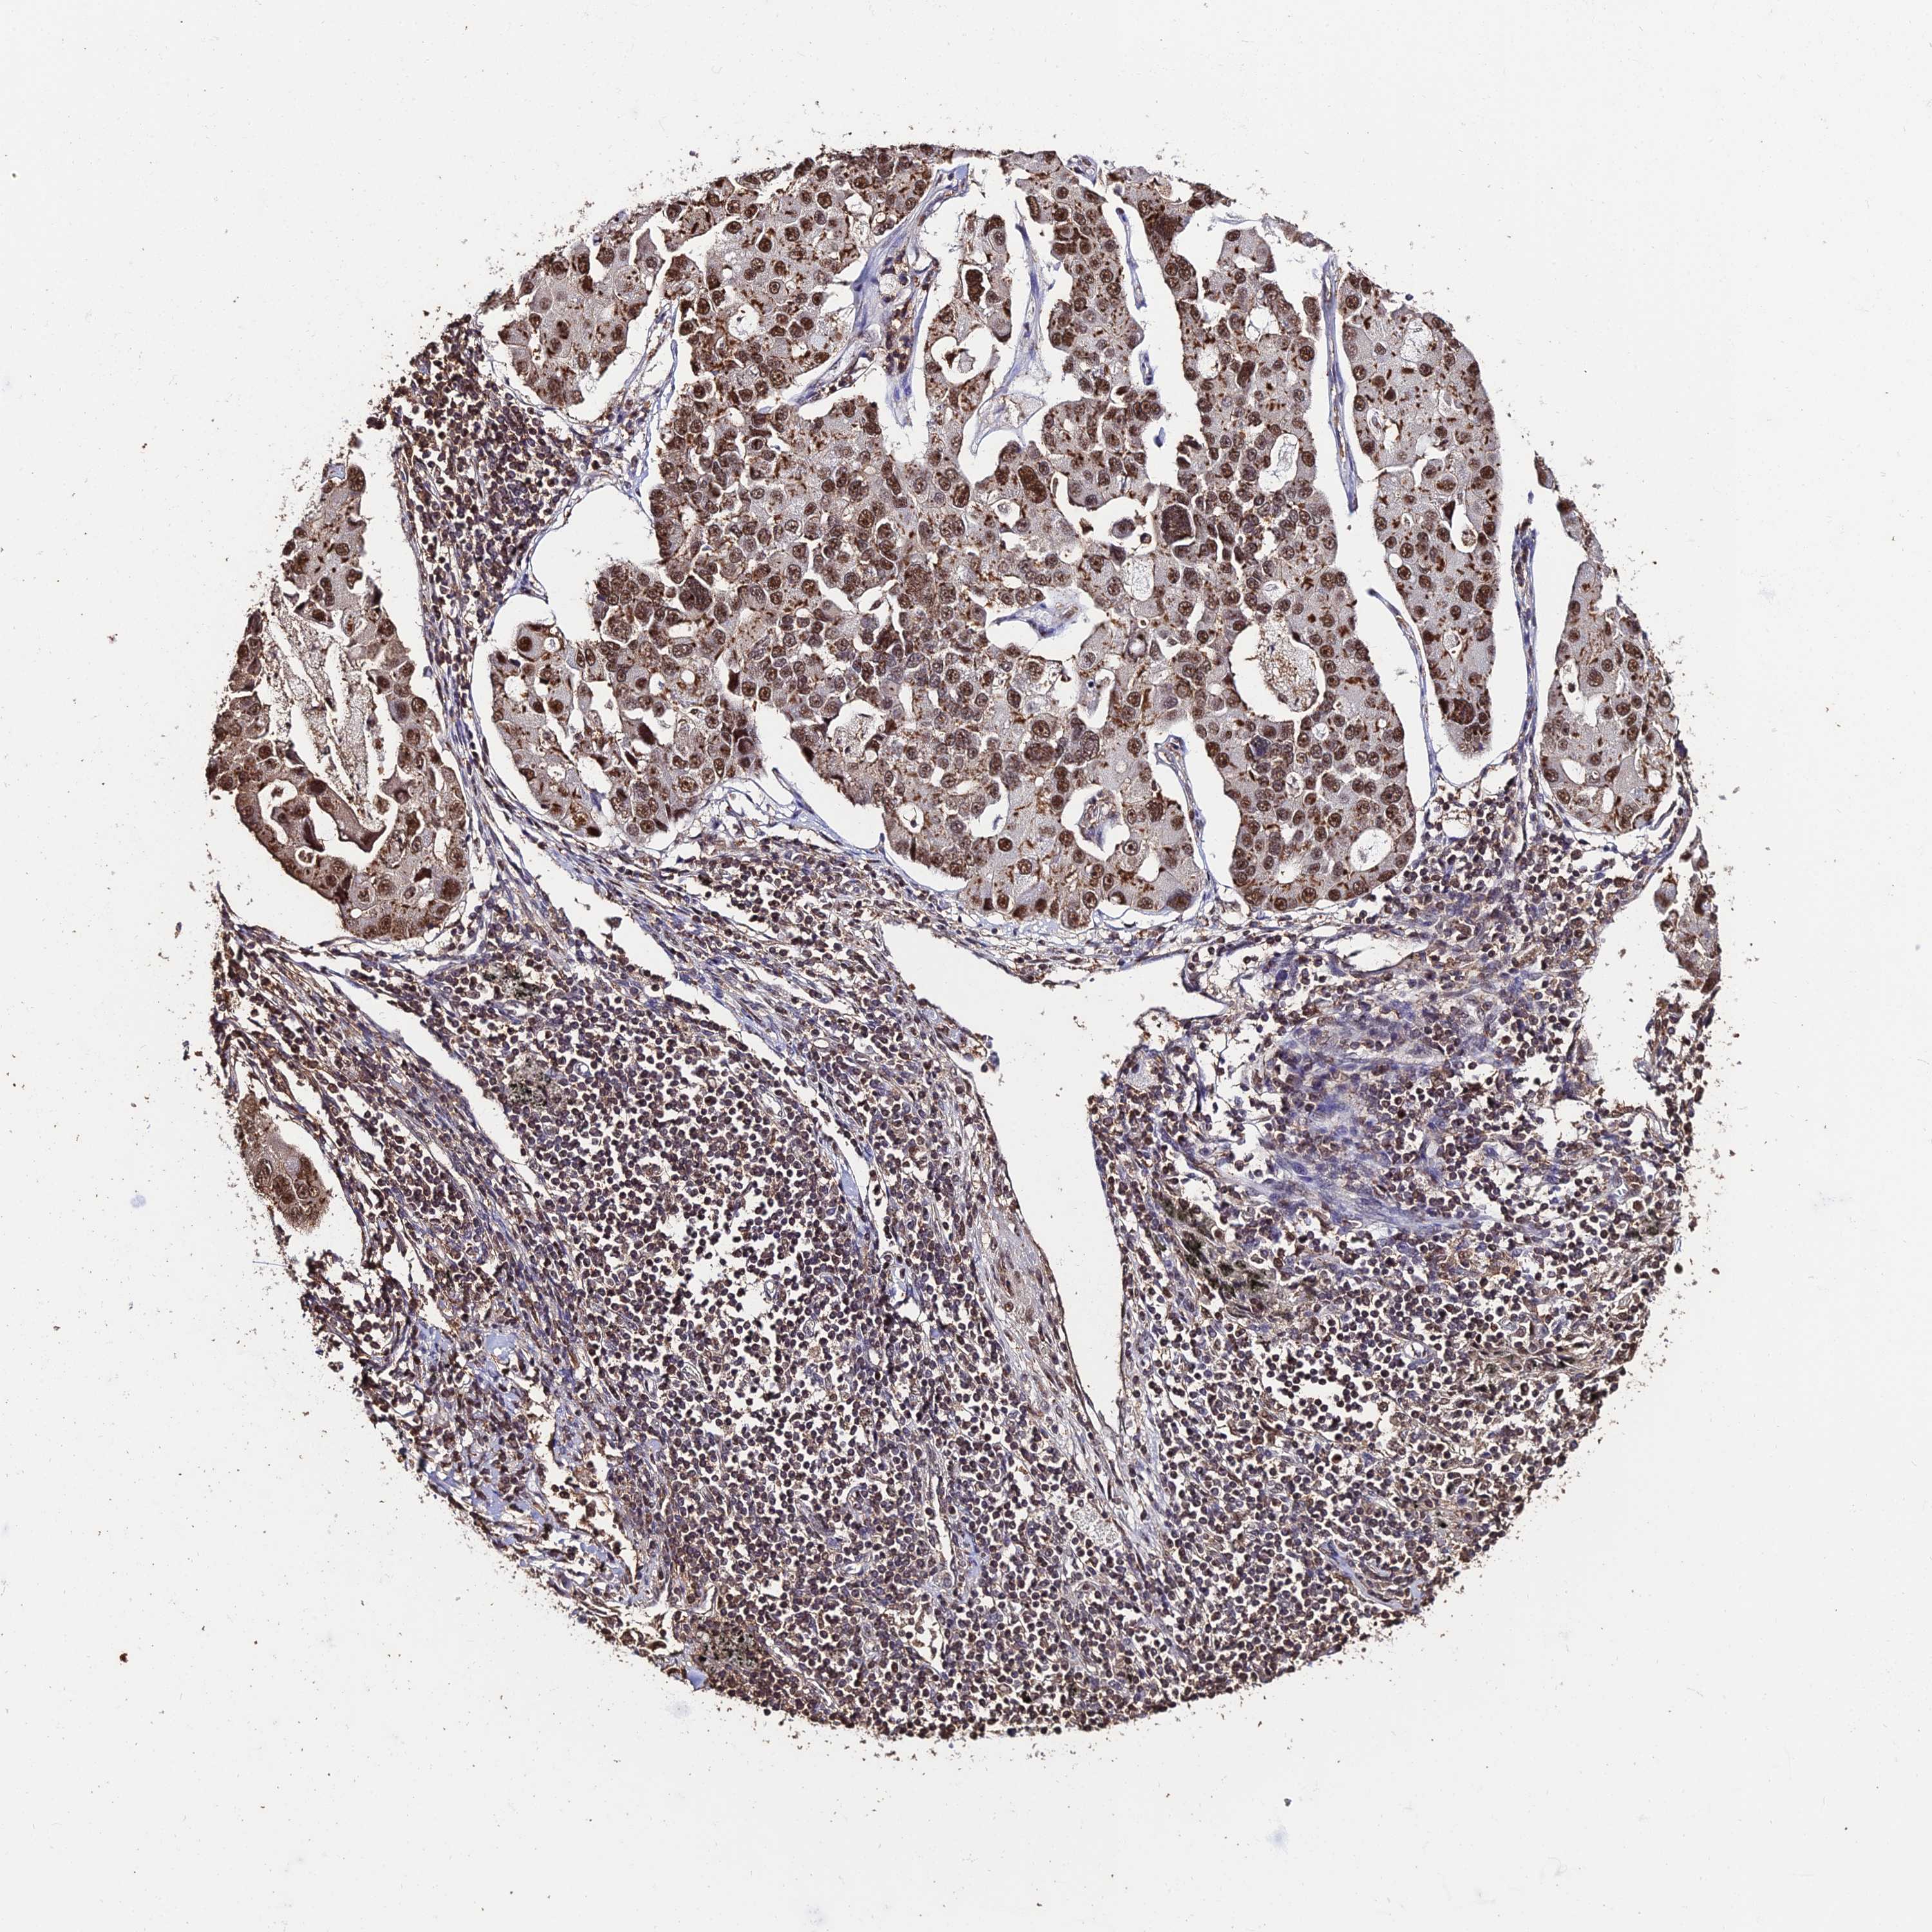

CANCER LUNG CANCER Show tissue menu